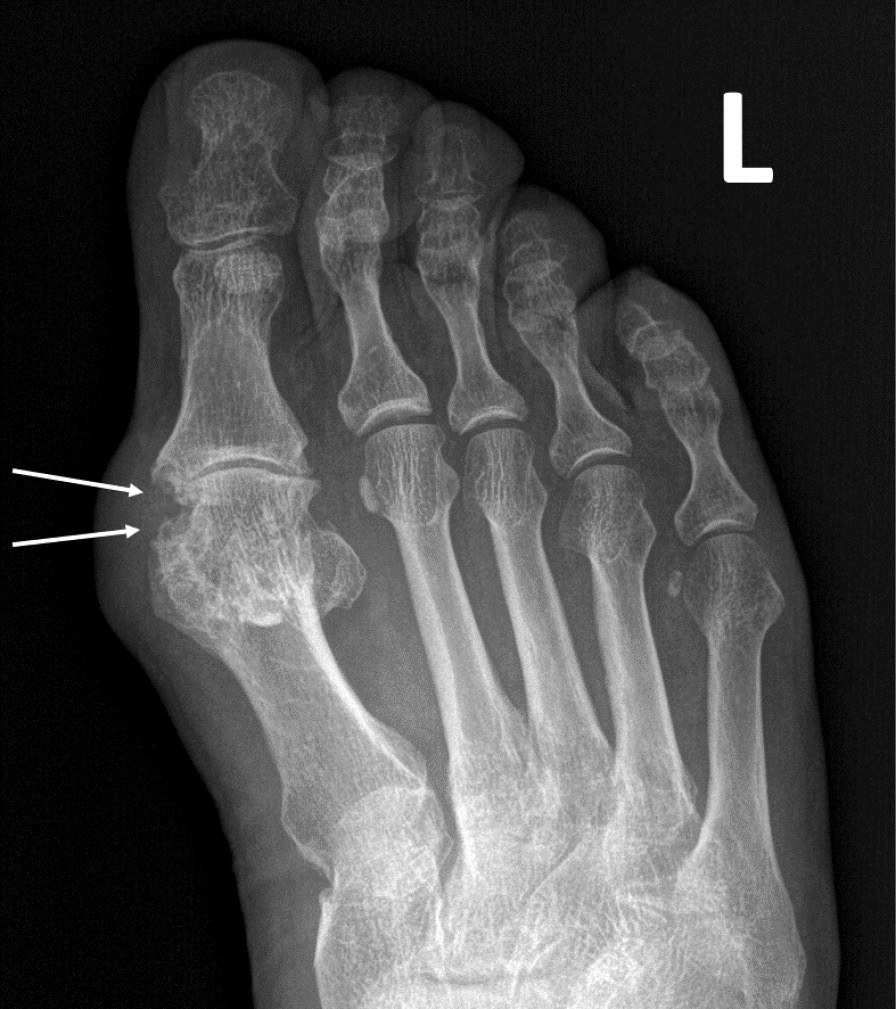

При компьютерной томографии органов грудной клетки данных за «свежие» очаговые и инфильтративные изменения не получено. Увеличения лимфатических узлов подмышечных областей, средостения, корней легких не выявлено. Отмечался усиленный грудной кифоз, обызвествление передней продольной связки, на всем уровне исследования определялись передне-боковые спондилофиты, а также анкилоз большинства реберно-поперечных суставов. По данным рентгенографии кистей (рис. 1, 2) и стоп (рис. 3, 4) диагностированы признаки эрозивного артрита, анкилоз суставов запястья. По данным МРТ крестцово-подвздошных суставов (КПС) определялся неравномерный анкилоз КПС, хрящи по суставным поверхностям неравномерной толщины, примерно на половине протяжении сустава отсутствуют, «суставной промежуток» облитерирован. Неравномерность и нечеткость контура суставных поверхностей за счет множества краевых эрозий справа, единичных – слева, с наличием остеокластоза, в нижнем отделе слева по смежным отделам определяются участки трабекулярного отека, данная находка клинически интерпретирована как двусторонний активный сакроилиит (рис. 5, 6).

Рис. 3. Рентгенограмма правой стопы в прямой проекции. Краевые эрозии суставных поверхностей первого плюсне-фалангового сустава и межфалангового сустава I пальца (стрелки), сужение суставных щелей. Вальгусная деформация I пальца стопы

Рис. 4. Рентгенограмма левой стопы в прямой проекции. Краевые эрозии суставных поверхностей первого плюсне-фалангового сустава (стрелки), сужение суставной щели. Вальгусная деформация I пальца стопы